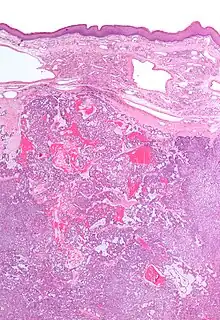

| Low magnification micrograph of a polymorphous low-grade adenocarcinoma, showing the typical variation of architectural arrangement. H&E stain. | |

- It has a varied microscopic architectural appearance, i.e. it is polymorphous.

PLGAs consist of a monomorphous cell population that has a varied histologic morphology.